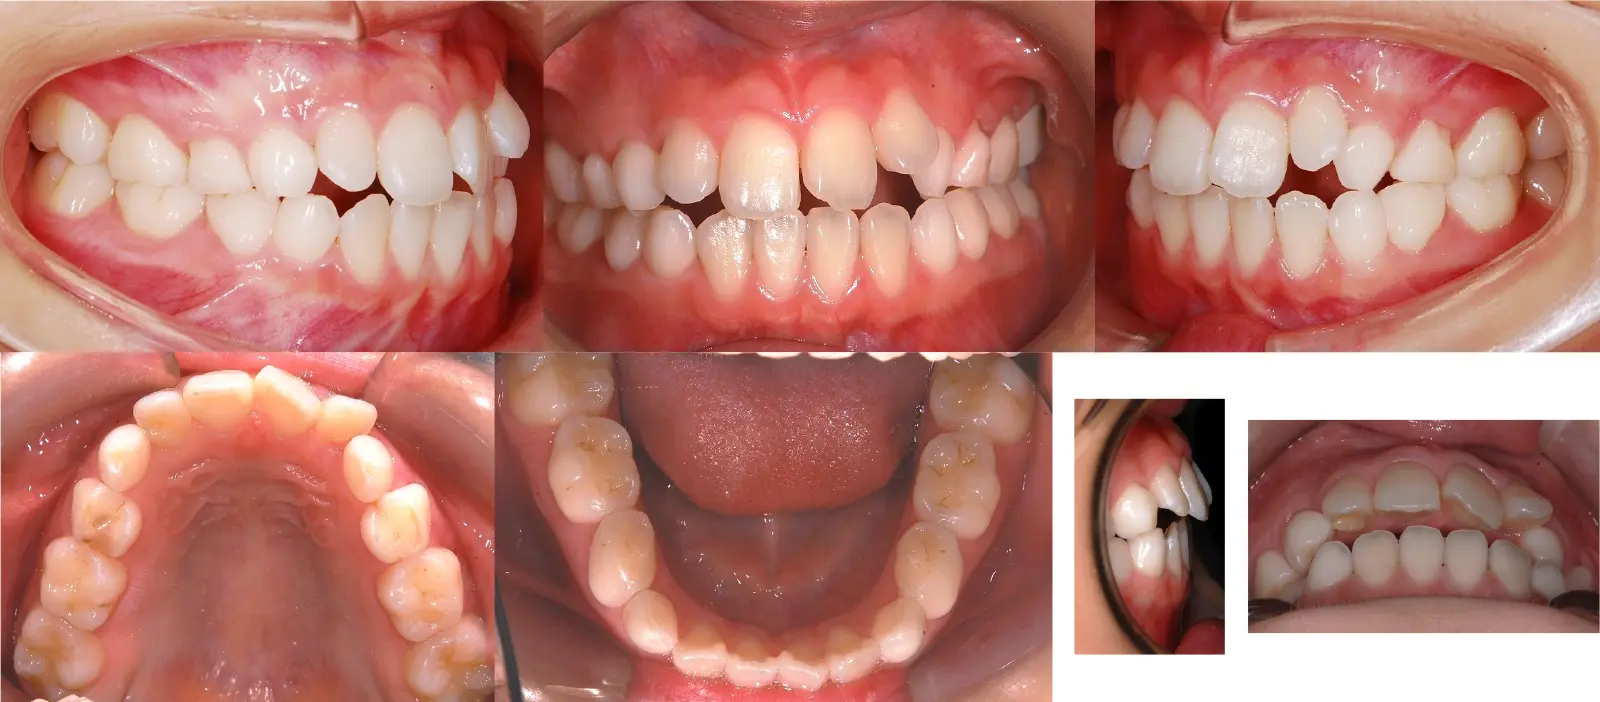

アングルⅠ級 反対咬合

第一段階の治療のみで、

永久歯は問題なく萌出し、安定している

- 主訴

1歯のみの逆破蓋

- 年齢

7歳

- 治療期間

6ヶ月

- 治療回数

6回

- 治療に用いた主な装置

2by2、拡大床

- 治療費

400,000円(税別)トータル料金

- 抜歯部位

非抜歯